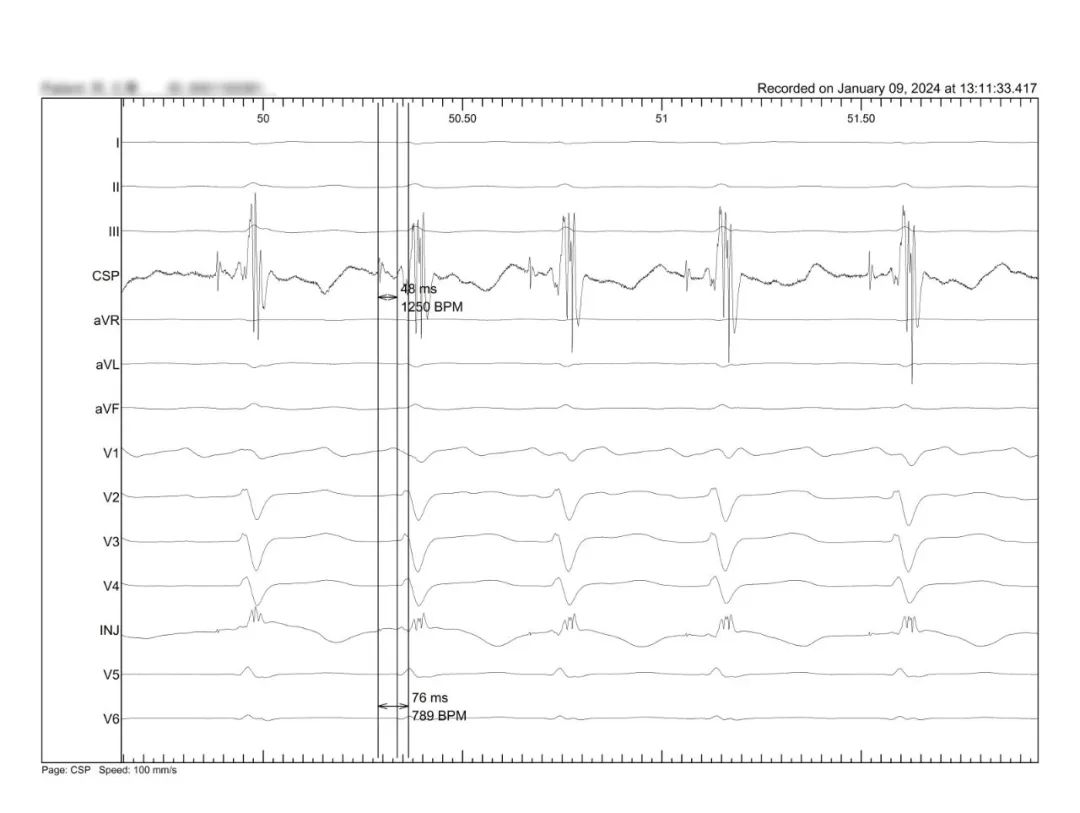

LBBP 术中S-NS变化

LBBP NS

LBBP S

AF快心室率心衰房室结消融电位损伤消融靶点

HISD电位

HISD 电位损伤